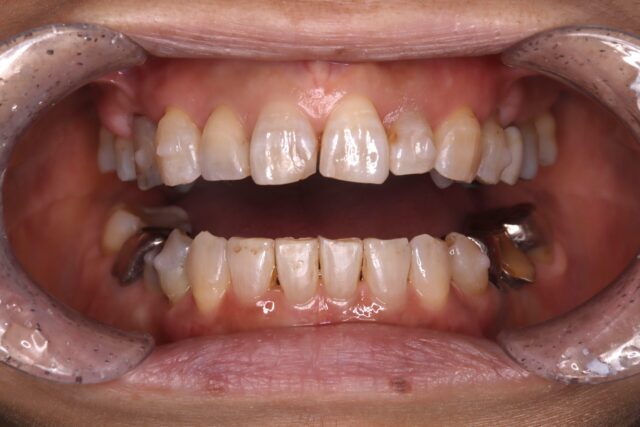

マウスピース矯正中

ガタガタがほどけてきている